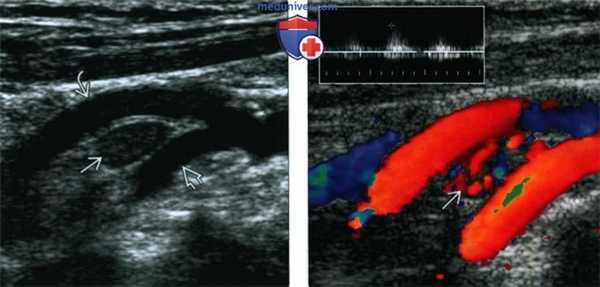

(Слева) УЗИ. В области бифуркации общей сонной артерии, между наружной и внутренней артериями, имеется гипоэхогенное образование с четкими контурами. Это небольшое образование было обнаружено случайно: пациенту выполнялась КТ по поводу травмы шеи.

(Справа) Этот же пациент, дуплексное сканирование. Очевидна сосудистая природа опухоли. Частотный анализ (на врезке) показал низкую сопротивляемость опухоли.